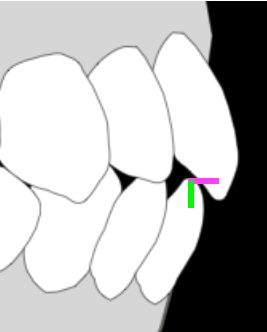

- オーバージェット、オーバーバイトが2、3mm

オーバージェットとは上の前歯先端と下の前歯先端の前後的な位置関係を表します。オーバーバイトとは上の歯と下の歯の重なる深さのことです。(ピンクの線がオーバージェット、緑の線がオーバーバイト) - 上下の歯が1歯対2歯で噛んでいる、全ての歯がしっかり当たっている